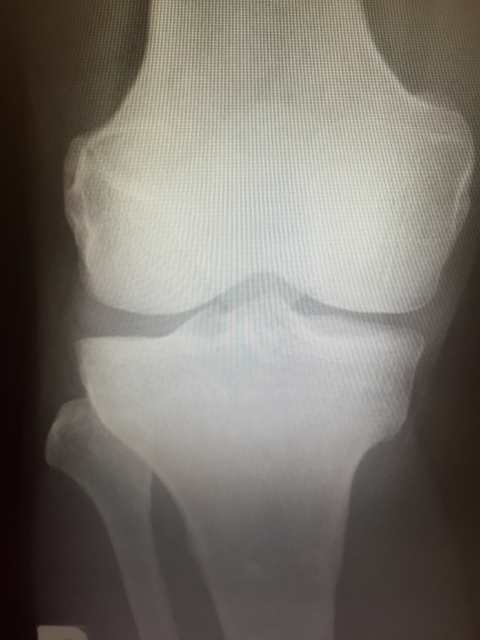

膝が痛くて病院に行き、『変形性膝関節症』と診断された70代の女性。

(※写真は本人のものではありません)

変形性膝関節症と診断されるということは、膝を構成する骨に変形がみられるということです。

この変形を元に戻すことはできません。

しかし、変形の程度が軽ければ、このように症状や痛みが楽になっていきます。

膝の関節に変形があっても、足首や股関節の状態をよくすることで、膝の負担を減らすことはできます。